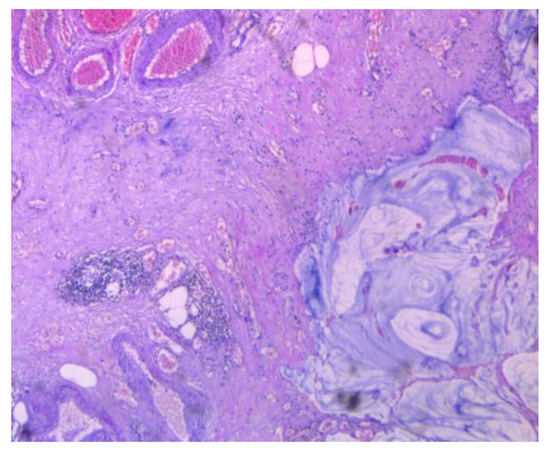

3.2.2. Clinical and Pathology Findings

3.1.1. Mucinous Cystadenoma

3.1.2. Mucinous Ovarian Cancer

3.1.3. Colon Cancer with Ovarian Metastasis

3.1.4. Malignant Transformation of an Ovarian Primary Mature Cystic Teratoma (MCT)